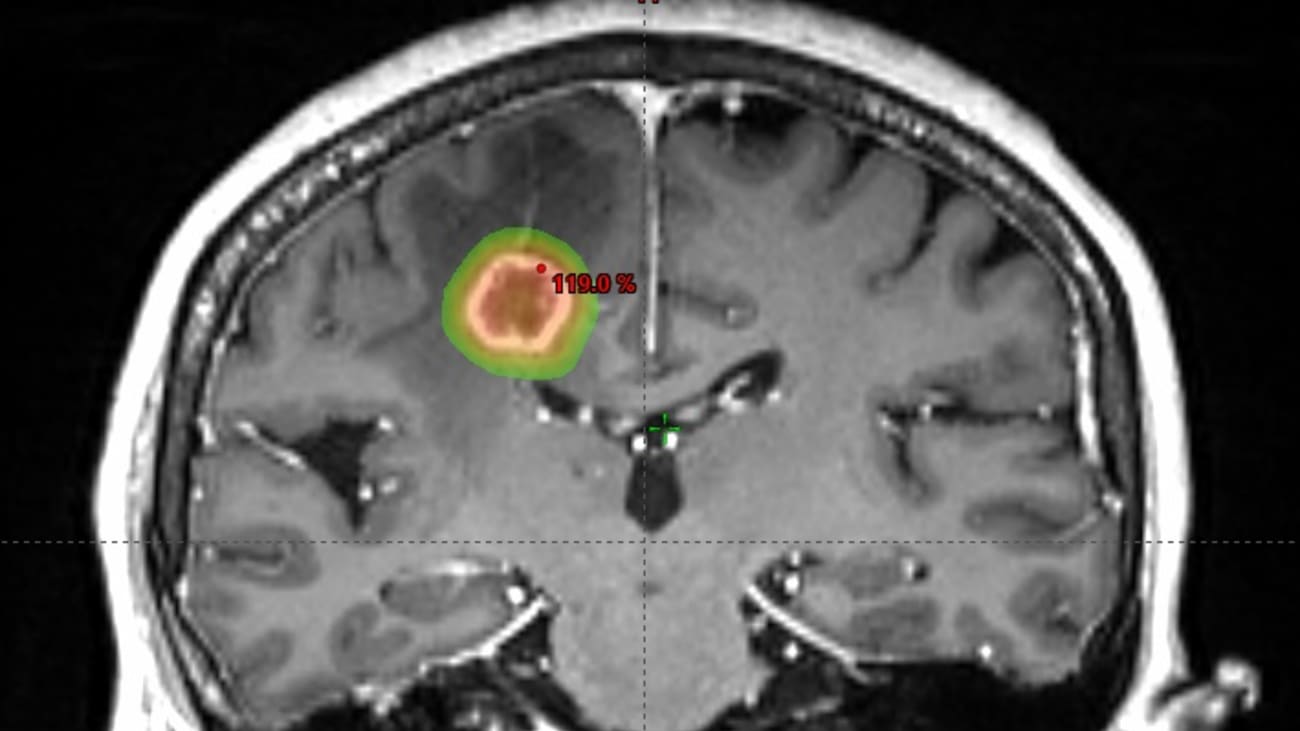

Images showing the Stereotactic Radiation Therapy plan which precisely targets several tumors in the brain with sparing of the normal brain.

SRS therapy is a minimally invasive surgical intervention that makes use of advanced 3D imaging to deliver highly focused beams of radiation to a specific target, such as a tumor.

Using SRS, Dr. Yeh and his team designed a treatment plan delivering focused, high-dose radiation to each lesion while sparing the surrounding healthy brain tissue.